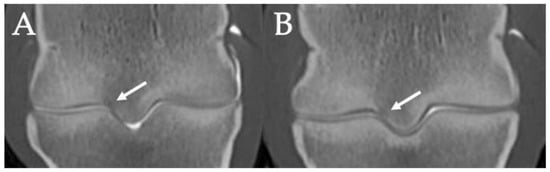

3.3. PSG Subchondral Bone Lysis